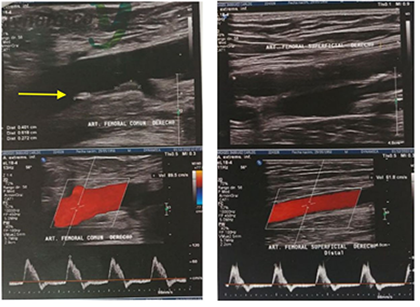

Por otro lado, ante la sospecha de una embolia por colesterol, se realiza una ecografía doppler arterial de miembros inferiores, la cual denota ateroesclerosis en fase inicial sin alteraciones hemodinámicas, presencia de placas mixtas no significativas en arteria femoral común (Figura 2).